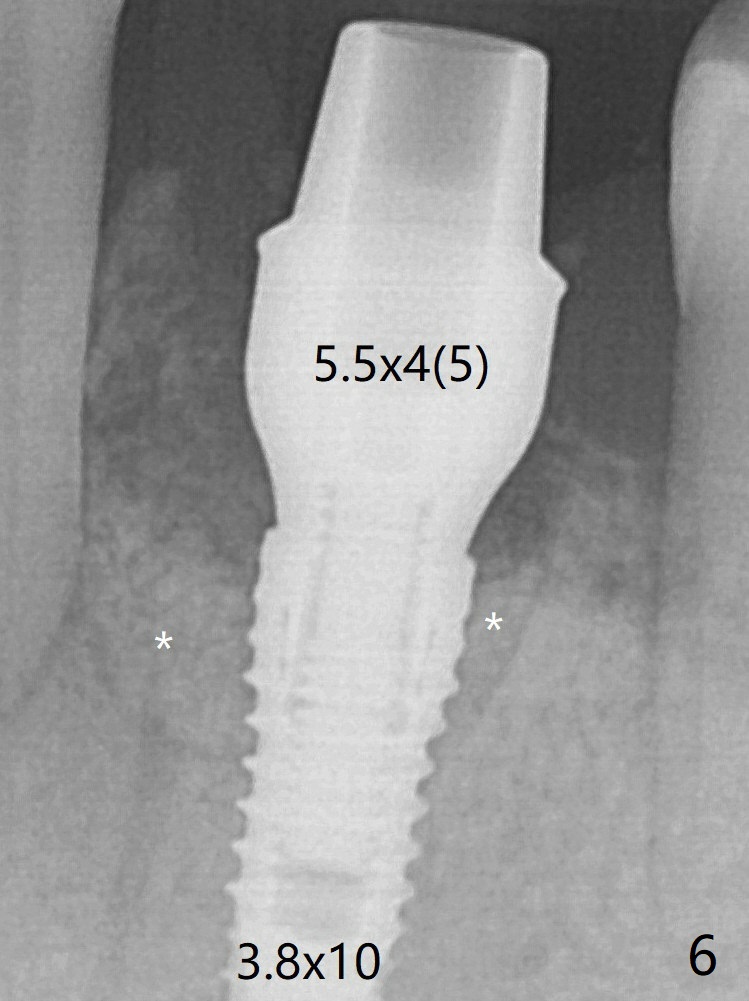

A 3.8x10 mm dummy implant is placed tentatively with an apical space (Fig.4 (the distal root surface of the lateral incisor is denuded (<)). When a same dimension definitive implant is placed with 40 Ncm, it is 2 mm below the lingual gingival margin, whereas 6-7 mm below the buccal one (Fig.5). Vanilla graft is placed before placement of a 5.5x4(5) mm abutment (Fig.6). The root surface of the lateral incisor is covered by the bone graft. Later the abutment is changed to a longer and smaller one (Fig.8) with more of the allograft (*). The short implant is chosen because it has to be placed deep to prevent periimplantitis, especially lingually, in spite of the fact of the unfavorable crown/implant ratio (Fig.4). The diameter of the implant is small so that there is ample space to pack bone graft both buccally and lingually. The majority of the bone graft seems to be in place 8 months postop (Fig.12).